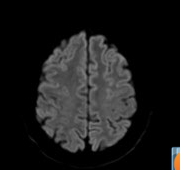

Video 1: axial difuzie

Clinica pacientilor in leziunile acute de corp calos este nespecifica si acesti pacienti ajung tarziu la medic si la examinari imagistice. In imaginile prezentate se evidentiaza mutiple plaje in hipersemnal T2 si FLAIR, hiposemnal T1 cu restrictie de difuzie a apei, pe alocuri cu priza de contrast de tip giral ce afecteaza corpul calos in treimea anterioara si substanta cerebrala de vecinatate. In literatura, cea mai frecventa leziune ischemica acuta a corpului calos este leziunea de splenius.

Leziunile de corp calos cu afectare parțială sunt greu de diagnosticat clinic deoarece simptomele sunt nespecifice – de aceea imagistica prin rezonanţă magnetică are un rol important. Corpul calos joacă un rol în integrarea inter emisferică, limbajul, inteligența și creativitatea indivizilor, prin urmare variații în dimensiunea corpului calos sunt observate în diferite boli neurologice, cum ar fi Alzheimer și tulburarea afectivă bipolară.